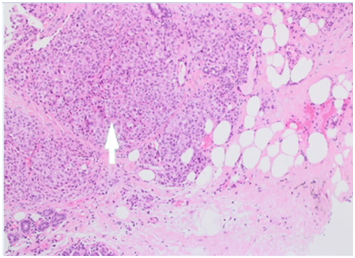

Figure 5(A) x2 magnification: normal breast lobules at 7’oclock, sheets of melanoma at the centre and necrosis with melanin pigment at 1’oclock.

Figure 5(B) x4 magnification: normal breast lobules at 7’oclock, sheets of melanoma at the centre and necrosis with melanin pigment at 1’oclock.